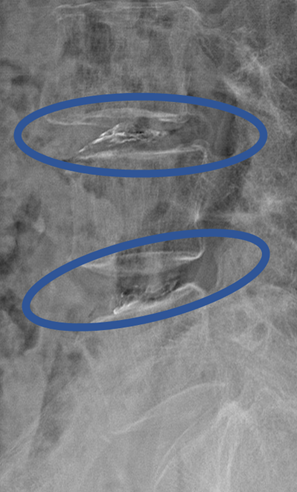

患者様と相談の元、 3/4、4/5 にセルゲル法を施行

DiscoGelを入れた後の画像になります。

治療は 30分 程度で終了

回復室で休憩後、歩いて帰院されました。